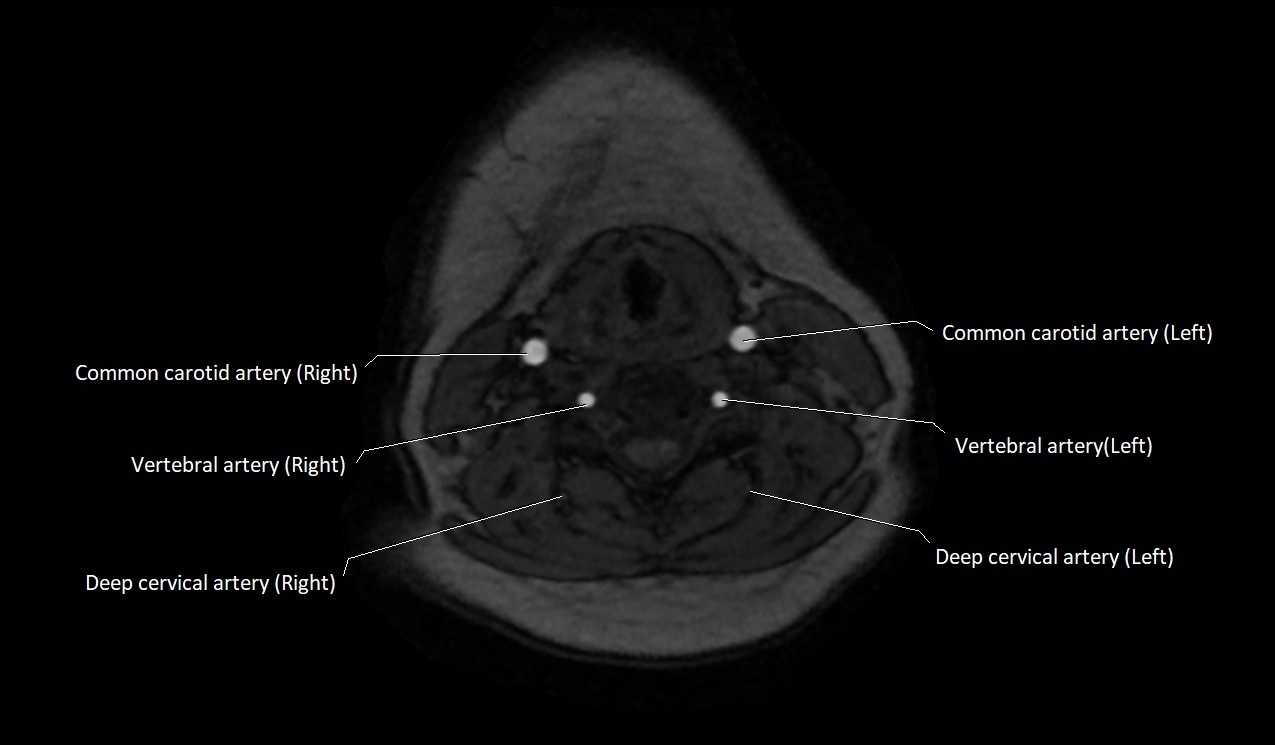

MRI images

image